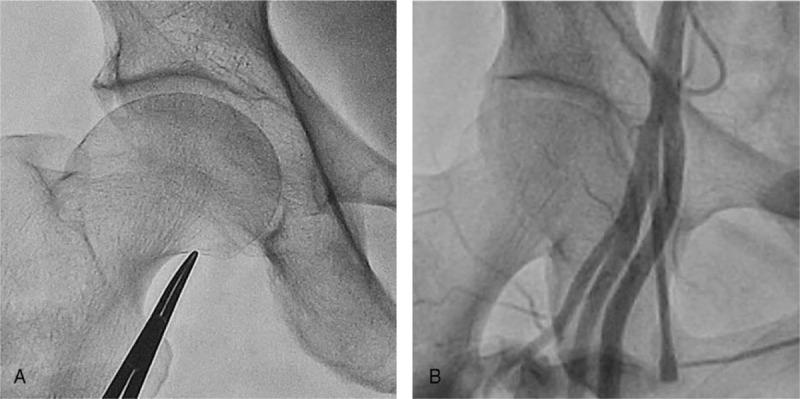

The inferior border of the femoral head (IBFH) is widely used as a landmark in femoral artery puncture during invasive coronary angiography (ICA). However, application of this technique can be challenging especially in obese patients. This study was performed to investigate the association between body mass index (BMI) and the risk of low puncture in femoral artery puncture.A total of 464 patients (64.8 ± 11.1 years, 55.8% male) who underwent ICA via trans-femoral access were retrospectively reviewed. IBFH was used as a landmark for a skin nick and the femoral artery cannulation site was confirmed by femoral angiography. Cannulation at the bifurcation of the common femoral artery (CFA) or below were considered low puncture.Twenty-nine patients (5.8%) were identified as having an angiographically high CFA bifurcation and low femoral artery puncture occurred in 27 (93.1%) patients of them. Among patients with normal bifurcation (n = 464), low puncture occurred in 74 (15.9%) patients. Underweight (BMI < 18.5 kg/m) or obese (BMI ≥ 30 kg/m) patients were more common in the low puncture group than in the proper puncture group (36.5% vs. 5.9%, P < .001). Multivariable analysis showed underweight or obesity (odd ratio, 9.10; 95% confidential interval, 4.77-17.35; P < .001) was an independent risk factor of low puncture even after controlling for clinical covariates. The average distance from IBFH to the CFA puncture site was shorter in patients with underweight (1.74 ± 0.71 cm) or obesity (1.75 ± 0.60 cm) than in those with normal BMI or overweight (2.07 ± 0.83 cm) (P = .030). Trigonometric calculation showed that the average distance from IBFH to the CFA puncture site was 0.5 to 2.59 cm (mean = 1.32 cm) shorter in underweight patients compared with those of normal weight or overweight patients.In patients with normal CFA bifurcation, underweight or obesity were associated with increased risk of low puncture. The puncture site should be chosen about 1 finger width more proximal to IBFH for ICA in such patients.

股骨头下缘(IBFH)在有创冠状动脉造影术(ICA)期间的股动脉穿刺中被广泛用作一个标志。然而,应用该技术可能具有挑战性,尤其是在肥胖患者中。本研究旨在调查体重指数(BMI)与股动脉穿刺时低位穿刺风险之间的关联。

对总共464例(年龄64.8±11.1岁,男性占55.8%)经股动脉途径接受ICA的患者进行了回顾性分析。以IBFH作为皮肤切口的标志,并通过股动脉造影确认股动脉插管部位。股总动脉(CFA)分叉处或其以下的插管被视为低位穿刺。

29例(5.8%)患者被确定为具有造影显示的高位CFA分叉,其中27例(93.1%)患者发生了低位股动脉穿刺。在分叉正常的患者(n = 464)中,74例(15.9%)患者发生了低位穿刺。与正确穿刺组相比,低位穿刺组中体重过轻(BMI < 18.5 kg/m²)或肥胖(BMI≥30 kg/m²)的患者更为常见(36.5%对5.9%,P <.001)。多变量分析显示,即使在控制了临床协变量后,体重过轻或肥胖(比值比,9.10;95%置信区间,4.77 - 17.35;P <.001)仍是低位穿刺的独立危险因素。体重过轻(1.74±0.71 cm)或肥胖(1.75±0.60 cm)患者从IBFH到CFA穿刺部位的平均距离比BMI正常或超重患者(2.07±0.83 cm)短(P =.030)。三角计算显示,与正常体重或超重患者相比,体重过轻患者从IBFH到CFA穿刺部位的平均距离短0.5至2.59 cm(平均 = 1.32 cm)。

在CFA分叉正常的患者中,体重过轻或肥胖与低位穿刺风险增加相关。对于此类患者进行ICA时,穿刺部位应选择在比IBFH更靠近近端约1指宽处。